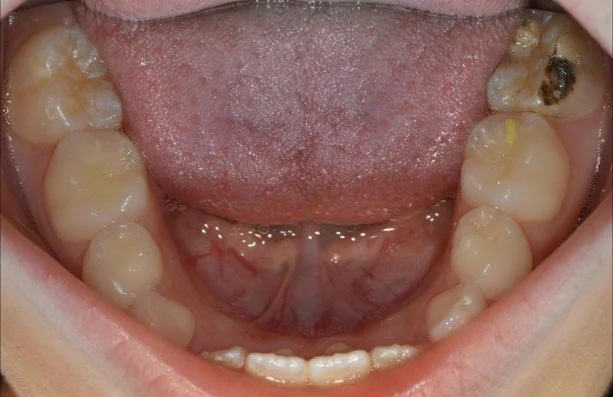

Post SDF treatment, unfortunately, it does stain it a bit black…